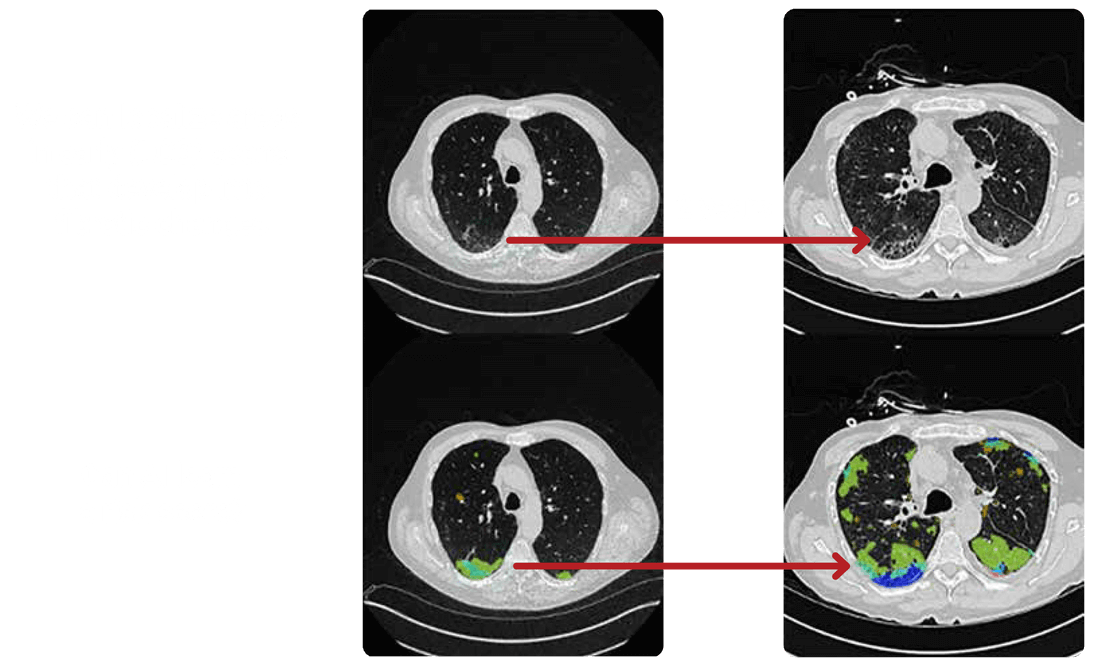

Learn how early-stage interstitial lung abnormalities (ILAs) detected in routine screenings can prevent progressive fibrotic lung disease. Discover the latest features of the OSIC Cloud platform, including advanced visualizations that highlight subtle lung changes, and hear vital insights from the Czech Republic’s national lung cancer screening program.

Discover how we can detect fibrotic lung disease before it becomes visible. Learn how AI and advanced imaging technologies are transforming pulmonary medicine. Explore the features of OSIC’s global data platform, which now houses over 7,000 fibrosis lung disease scans, and find out how these advancements facilitate earlier interventions for high-risk patients.

Training AI to Detect ILA

Can we predict which ILAs will progress to ILD?

OSIC is enabling researchers to train deep learning models to do just that.

• Early ILA detection using LDCT and HDCT

• Stratification of “at-risk” populations

• Potential for earlier treatment and better outcomes

AI + OSIC = New frontiers in preventive pulmonology